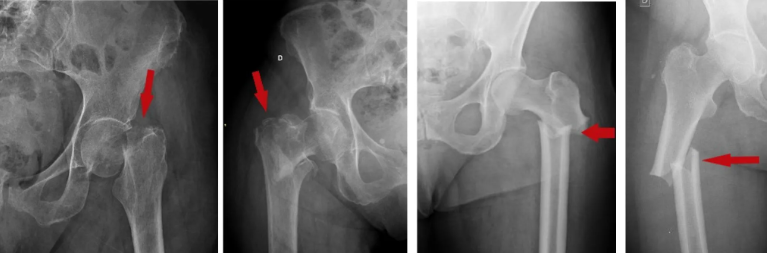

Fraturas Bilaterais de Fêmur

A apresentação clínica clássica revela membros inferiores encurtados, rodados e com deformidade visível.

- Risco Hemodinâmico: O compartimento da coxa pode comportar até 1,5 litros de sangue por fêmur fraturado. Uma fratura bilateral pode causar a perda de 3 litros de sangue, levando rapidamente a um choque hipovolêmico classe III ou IV.

- Conduta: Reposição volêmica imediata, alinhamento com tração e imobilização. A cirurgia deve ser precoce. Se for lesão isolada, opta-se pela fixação definitiva (ex: haste intramedular); em pacientes instáveis (politraumatizados), opta-se pelo Damage Control (Controle de Danos) com uso rápido de fixador externo.